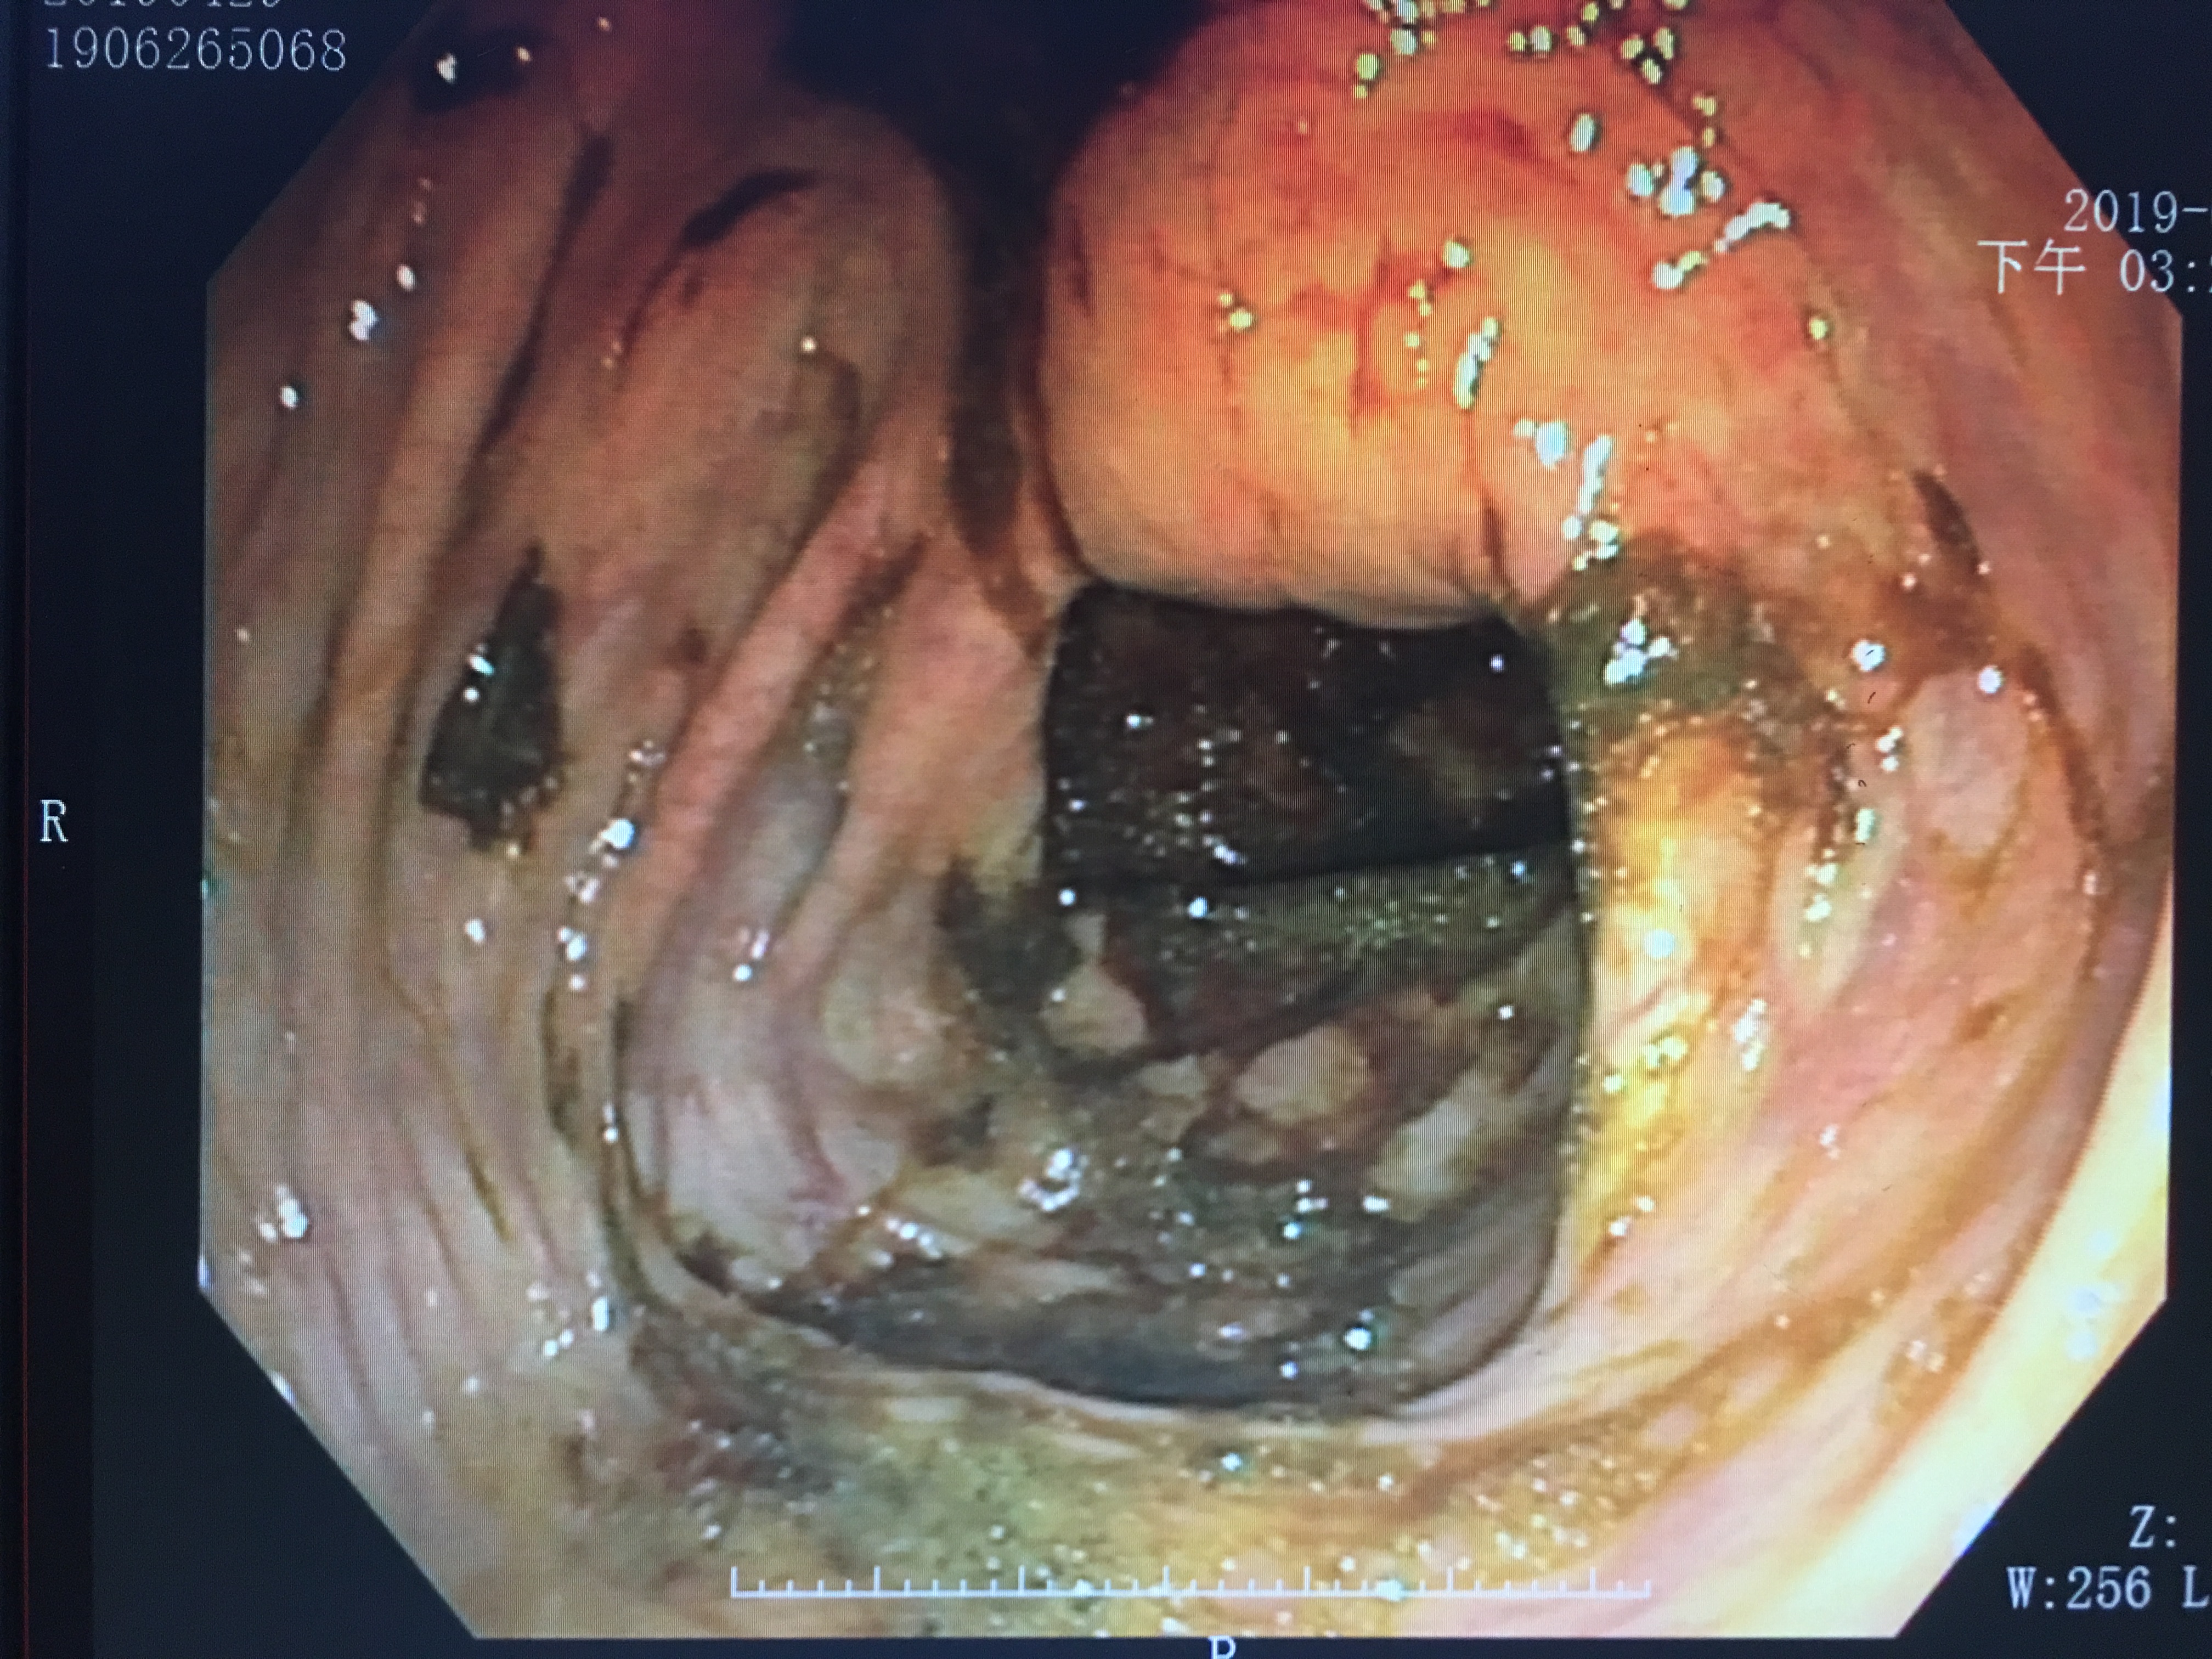

做肠镜,肠道准备一定要做足

胃镜检查是“不给进”,而肠镜不但“不让进”还需要“拼命出”。

肠镜检查的前一天,医生一般会开一大瓶“泻药”,让你不断拉肚子“拉到干净”为止。怎样才算干净?需要禁食,而且不断的喝下“泻药”,直到拉出来的是清稀的水样便为佳,这样肠道“清洁干净”后,通过肠镜检查就能很清晰的看到其中的情况了。

肠道准备的好的镜下

肠道准备欠佳的镜下

通过两张图片的对比,可以明显看出,肠道准备做的好镜下可以清晰看到肠壁的情况,而肠道准备欠佳的则由于食物残渣、粪便等覆盖影响而部分肠壁显示不清,甚至因为肠道准备不充分的缘故,掩盖了病变的部位,而造成漏诊等。